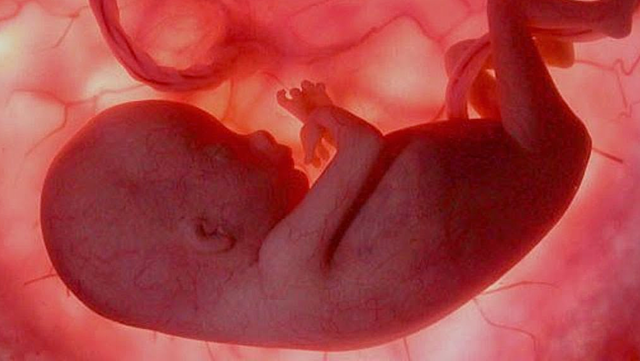

• Semana 11

Semana 11

A la semana 11 del embarazo el bebé pesa aproximadamente 8 gramos y su tamaño será entre 4 y 6 centímetros. Vamos a poder ver grandes cambios a partir de ahora, sus dedos ya los podrán ver separados gracias a que las membranas que los unían han desaparecido.

• Semana 12

Semana 12

El bebé ya se mueve dentro de la mujer y ya es capaz de estirarse y dar pequeñas pataditas. Si es el primer embarazo aún es pronto para que las mujeres noten esta sensación de hormigueo . Pero las mujeres que ya tienen su segundo embarazo ya pueden sentir esta sensación alrededor de las 12 semanas. Él bebe ya puede tener 10 semanas de vida y mide 6,5 centímetros y pesa 18 gramos. Él bebe ya se pude alimentar a través del cordón umbilical, recibiendo ya nutrientes y oxigeno